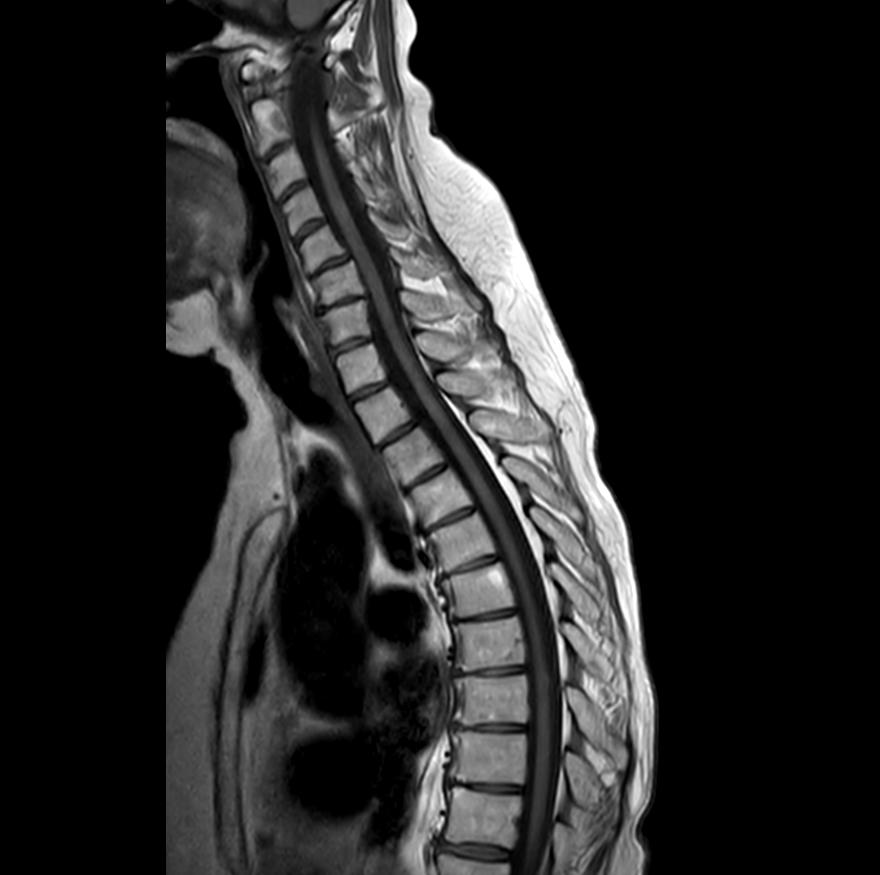

Si descrive il caso di una paziente di 62 anni affetta da metastasi encefaliche e midollari da neoplasia mammaria HER2 positiva. La sua storia oncologica ha inizio ad Ottobre 2018, quando un’ecomammografia di screening mette in evidenza la presenza di un’opacità a margini spiculati di 25 mm al quadrante supero-esterno della mammella sinistra. Una successiva risonanza magnetica (RM) di approfondimento mostrava altresì multiple adenopatie ascellari, retroclaveari e nella regione mammaria interna, nonché un’iniziale quadro di mastite. Si eseguiva pertanto agobiopsia, che deponeva per carcinoma duttale infiltrante scarsamente differenziato (G3), HER-2 positivo e non ormonoresponsivo, ovvero: ER 0, PgR O, HER-2 score 3+, ki67 25%. La stadiazione sistemica risultava negativa, con stadio clinico cT2N3M0 (IIIC). La paziente avviava quindi trattamento neoadiuvante con combinazione di chemioterapia (EC 90 per 4 cicli e a seguire paclitaxel settimanale per 12 cicli) e terapia target (trastuzumab), che proseguiva fino all’intervento chirurgico di mastectomia e dissezione ascellare, il cui esame istologico definitivo mostrava risposta patologica completa in sede mammaria e linfonodale. Proseguiva trastuzumab adiuvante fino alle 18 infusioni complessive. Eseguiva inoltre radioterapia su parete toracica, regione claveare e catena mammaria interna, con somministrazione di 50 Gy in 25 frazioni. Tuttavia, a soli 7 mesi dal termine del trattamento adiuvante, per insorgenza improvvisa di vomito e instabilità della marcia, la pa-

ziente accedeva in Pronto Soccorso, ove una risonanza magnetica dell’encefalo riscontrava multiple lesioni secondarie cerebrali. La paziente veniva quindi sottoposta a radioterapia panencefalica. Si avviava trattamento eziologico sistemico con trastuzumabemtansine (TDM-1), proseguito da Novembre 2020 per 28 mesi, ottenendo stabilità di malattia e buona tolleranza (episodica piastrinopenia G1). A Maggio 2024 la paziente lamentava ricomparsa di instabilità della marcia ed ipostenia degli arti superiori e inferiori, evolutisi nell’arco di 72 ore in completa impossibilità alla deambulazione, alla quale si associavano incontinenza urinaria e fecale. Recatasi in Pronto Soccorso, la

paziente veniva sottoposta a tomografia assiale computerizzata (TC) dell’encefalo, non dimostrativa, e a RM encefalo e rachide, la quale deponeva per disseminazione liquorale olo-cordica di neoplasia nota in anamnesi e multiple localizzazioni intraventricolari. Previa discussione multidisciplinare, si avviava trattamento di seconda linea con trastuzumab deruxtecan 5,4 mg/kg endovena ogni 21 giorni. La prima rivalutazione radiologica (20/08/2024) ha evidenziato la pressoché completa regressione delle lesioni ripetitive intra-midollari ed intraventricolari precedentemente descritte (figure 1 e 2). Permanevano riconoscibili unicamente due piccole lesioni focali all’altezza del passaggio T2-T3 e del passaggio T7-8, entrambe in riduzione dimensionale. Attualmente la paziente sta proseguendo il trattamento, con beneficio clinico ed iniziale ripresa della mobilità.